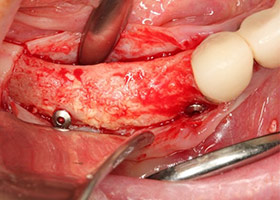

![proimages/case/Artificial_implant/HON04-1.jpg proimages/case/Artificial_implant/HON04-1.jpg]()

6.完成補骨手術。